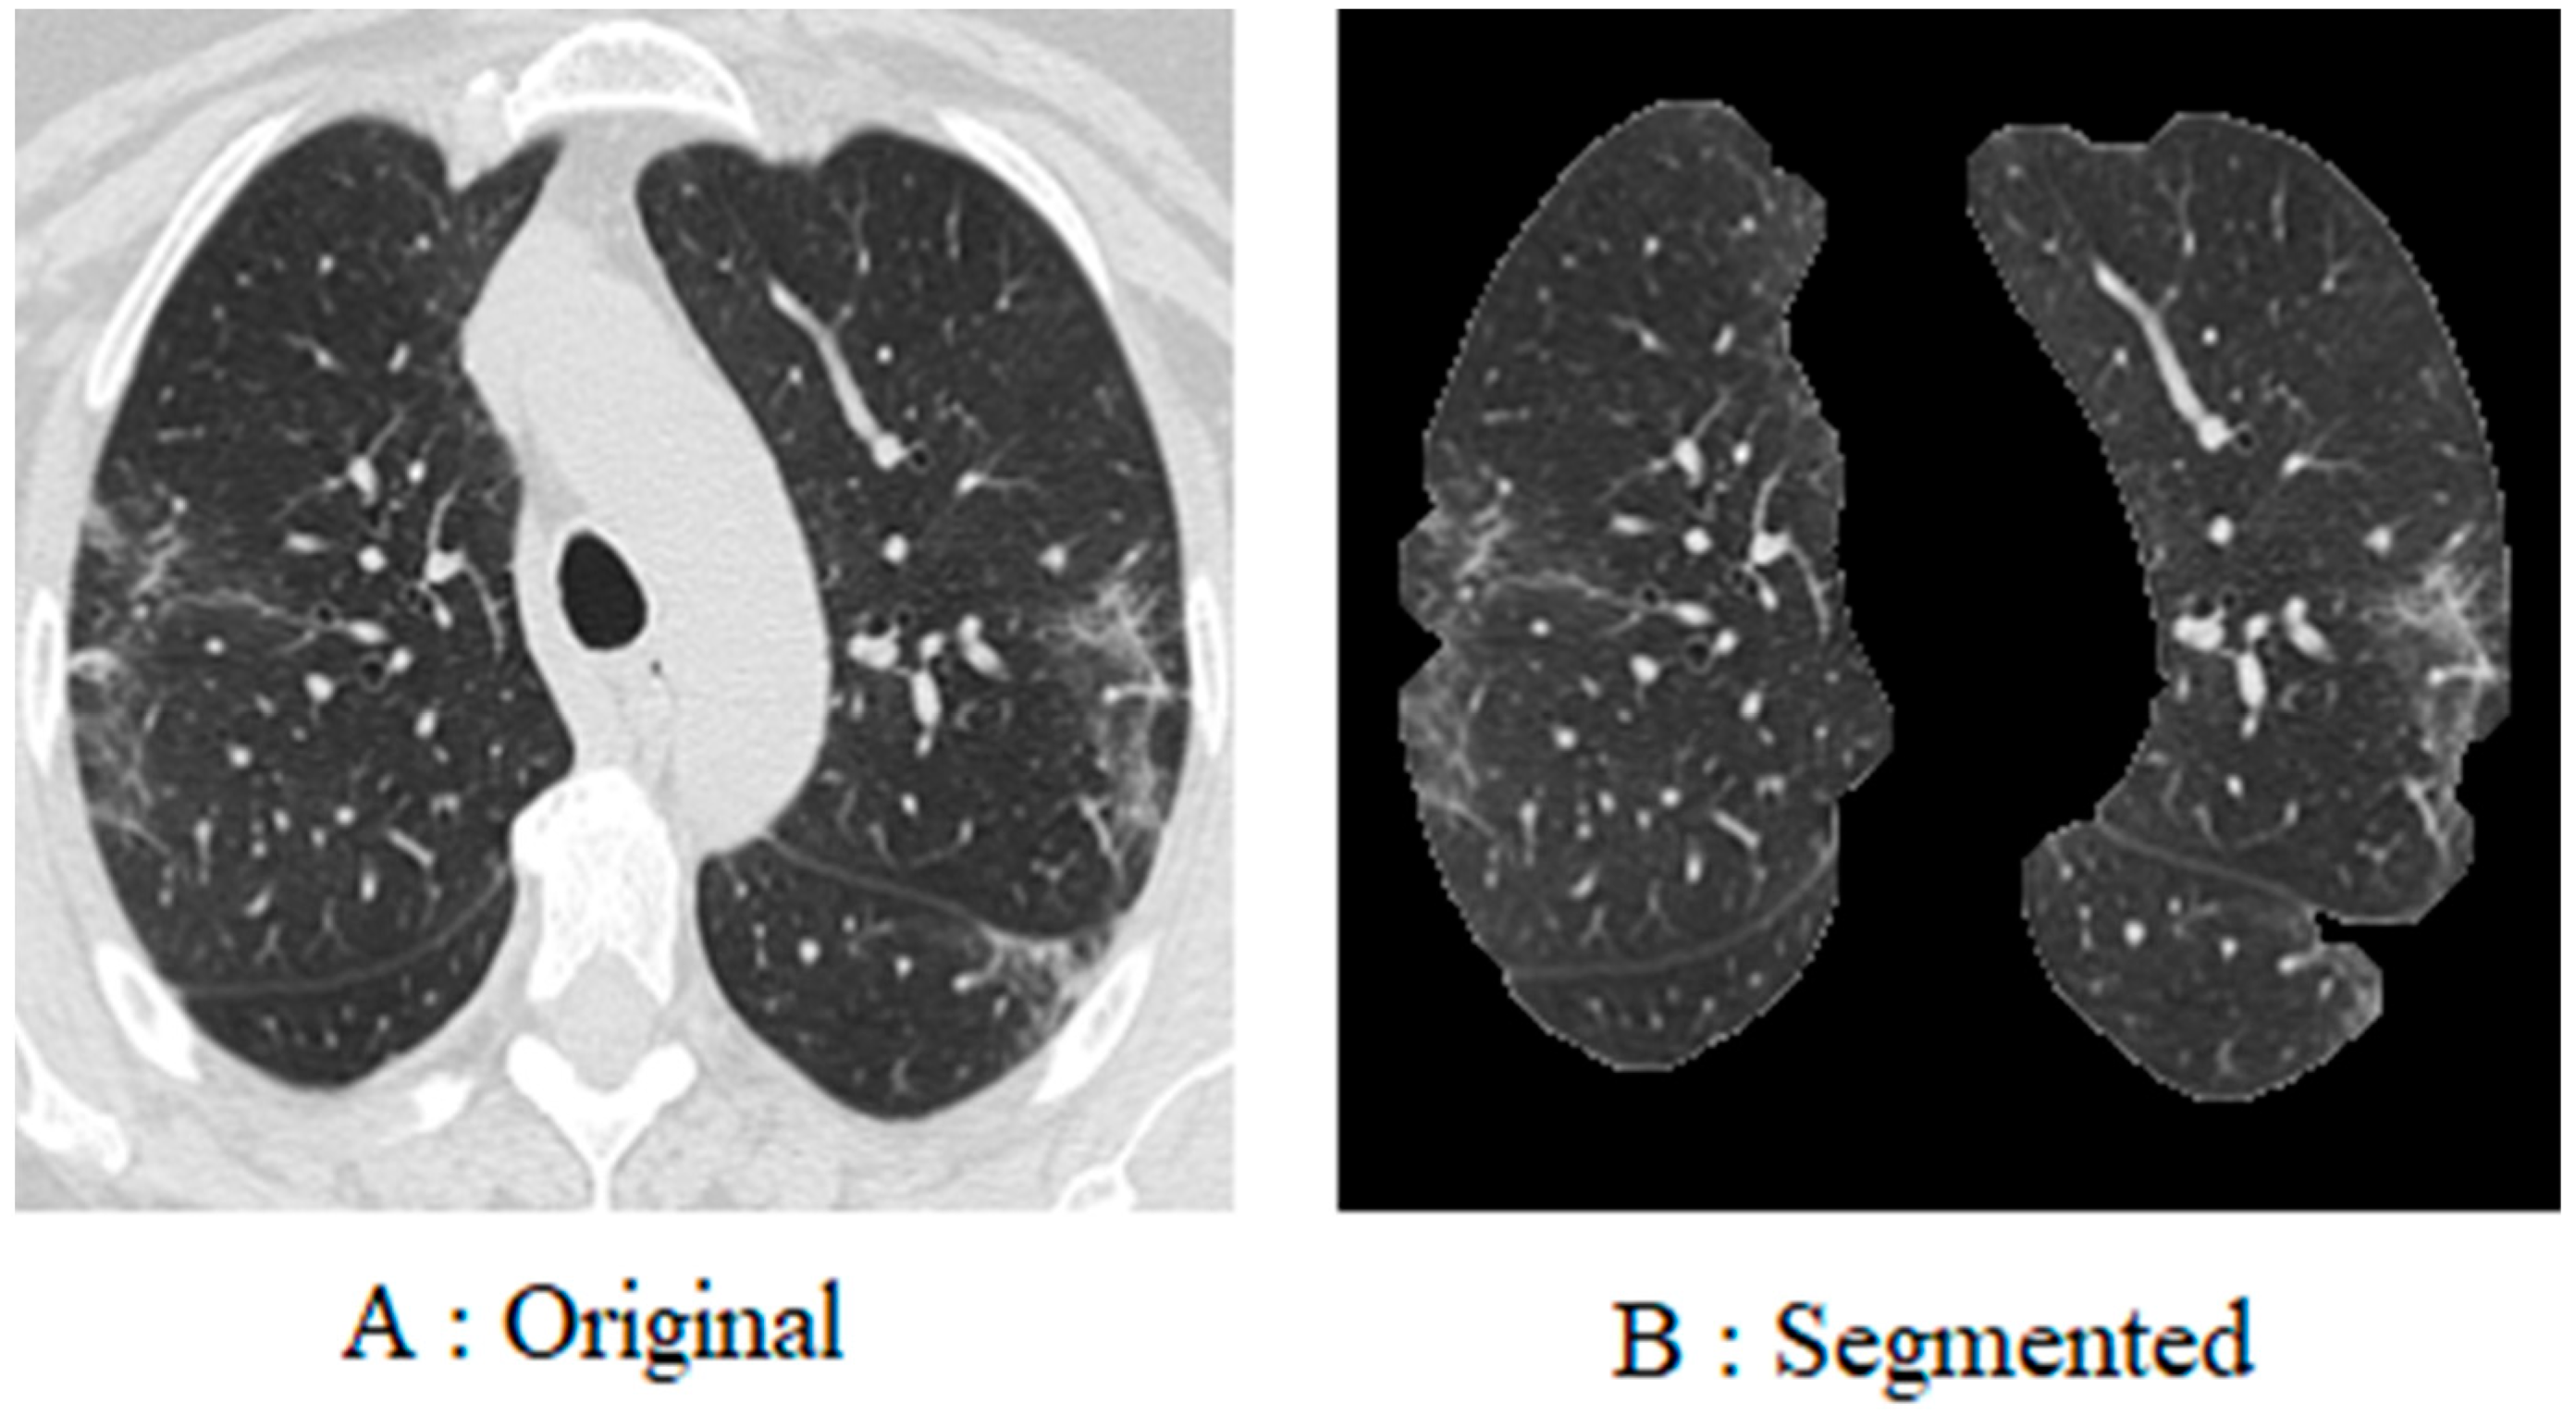

To begin with, every image in the database was resized to 200 × 200 pixels. This is due to the fact that the images in the database are of different sizes, and each image has a different number of pixels. Furthermore, since coronavirus is a lung disease, it is imperative to distinguish lung areas from other body parts. In other regions of the image, white borders can be seen that were derived from the original image using K-means segmentation and morphological methods. The lung image is illustrated in Figure 4, following the application of the pre-processing method.

Figure 4. This figure illustrates the contrast between the image prior to and following the implementation of pre-processing procedures. The raw image of the lung of a person infected with COVID-19 (A); the image of the lung after pre-processing (B).

Fractalfract 08 00237 g004